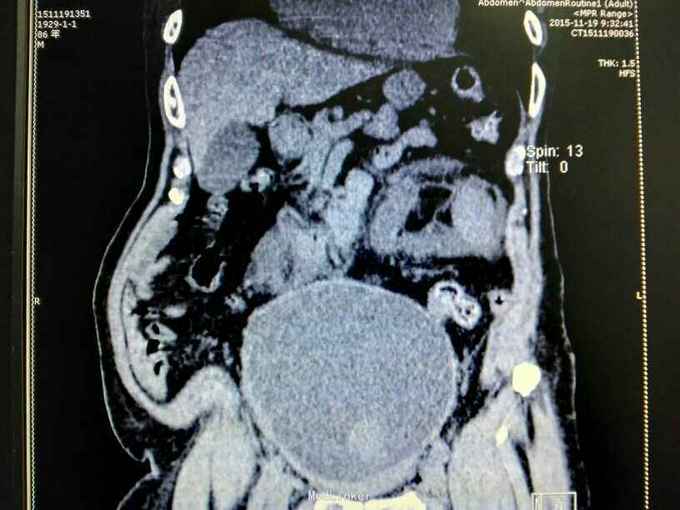

男性,87岁,进行性排尿困难10年,小便不能自解2天入院。无血尿,无发热、腰痛。一直口服藏药治疗前列腺增生症。既往无高血压、糖尿病。

腹部明显膨隆。耻骨上膀胱区扣浊。肾区无扣痛。尿常规少许白细胞。肌酐506,电解质正常。Hb116。

前列腺增生症 尿潴留 双肾积水 肾功能不全,膀胱结石,尿路感染,双肾多发囊肿。给予留置导尿,间断分次放尿后,出现肉眼血尿,持续膀胱冲洗,颜色较红,伴血凝块间断堵管。